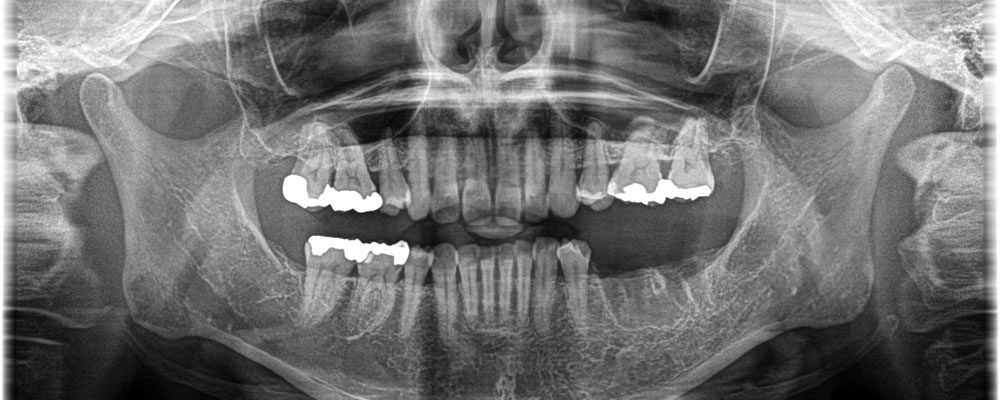

保存不可能な歯を抜歯後にインプラント治療を実施した症例

年齢

30代

性別

女性